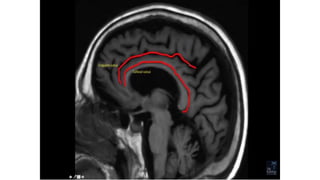

SULCI & GYRI

SULCUS IS THE DEPRESSION [VALLEYS]

AND

GYRUS IS THE RIDGE [HILLS]

Fissure/sulcus Importance

• Interhemispheric fissure • Separates two lobes

 Sylvian fissure/ Lateral

Sulcus

 Frontal to temporal

 Central sulcus  Frontal to parietal

 Callosal sulcus

 Cingulate sulcus

 Interparietal sulcus

 Parieto occipital sulcus

 Calcarine sulcus

The central sulcus-The sigmoid hook

The pars bracket sign- Parieto occipital sulcus

Fish tail- parieto occipital sulcus

Pars marginalis

The bifid sulcus

The intraparietal sulcus